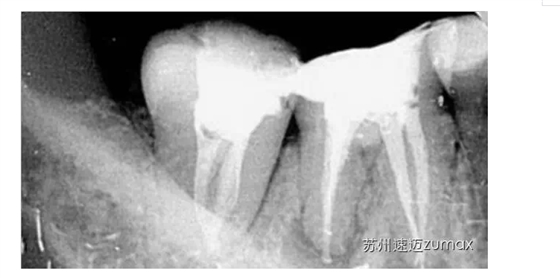

C形根管的治療最好是在手術(shù)顯微鏡下進(jìn)行。上橡皮障后開(kāi)髓,去除髓室中的牙髓組織,使用DG16仔細(xì)探查根管口位置,然后用10或15號(hào)不銹鋼K銼探查根管的形態(tài)、直徑和走向。當(dāng)根管口呈連續(xù)的C形時(shí),插入根管內(nèi)的診斷銼為2~4個(gè),通常為3個(gè)。當(dāng)根管口呈分號(hào)形時(shí),可以在較小的根管內(nèi)插入1個(gè)診斷銼,在較大的根管內(nèi)插入1~3個(gè)診斷銼。